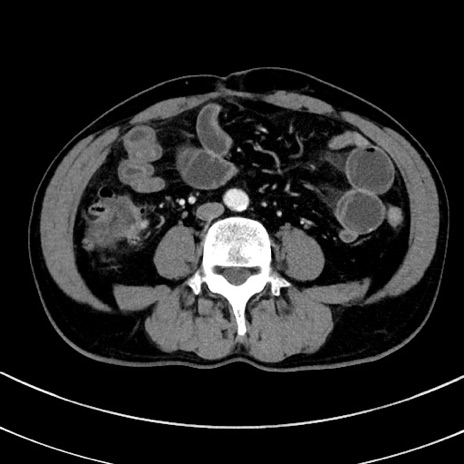

症例8(横断像)

【症例】 60歳代男性

【主訴】 黒色吐物

【現病歴】 4日前から嘔気自覚、2日前の朝食後にも嘔気あり、自分で手で嘔吐反射起こし嘔吐したところ血が混ざっていたため受診。

【既往歴】 5年前汎発性腹膜炎を伴う急性虫垂炎で手術、高血圧、前立腺肥大症、高脂血症

【身体所見】 腹部正中に手術癩痕あり 腹部平坦・軟圧痛なし膨満感あり

【データ】WBC 8400、CRP 4.54